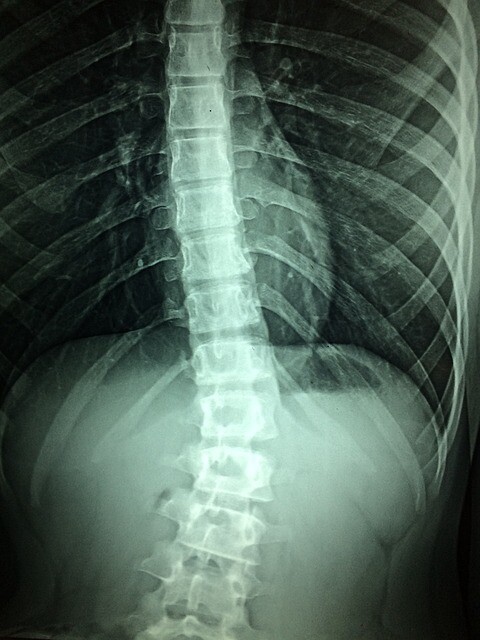

事故で下半身不随になった患者3人に、新開発の脊髄インプラントを埋め込んだところ、

再び歩けるようになったとする研究論文が7日、医学誌ネイチャー・メディシン(Nature Medicine)に掲載された。

脳波に似せた電気刺激を筋肉に送る仕組みで、重度の脊髄損傷患者の再起に道を開く可能性がある。

今回、患者3人はいずれも長さ6センチのインプラントを装着。電気信号を調整した後、すぐに歩行が可能になった。